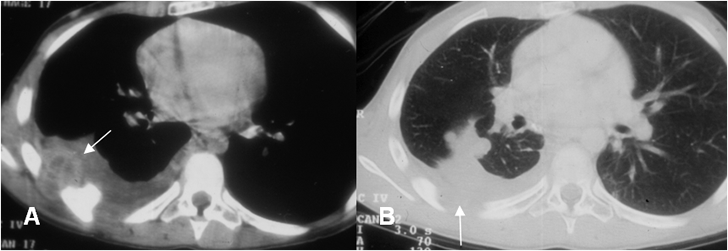

Fig 127. Sarcoma de Ewing.

A: TAC axial en ventana de tejido y B: TAC axial en ventana de hueso. Tumoración de localización extrapleural, la cual destruye los arcos costales y que corresponde a sarcoma de Ewing.